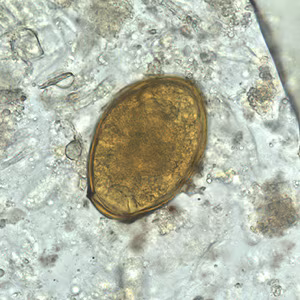

Eggs of Paragonimus spp. in unstained wet mounts.

Diagnosis is based on microscopic demonstration of eggs in stool or sputum, but these are not present until 2 to 3 months after infection. (Eggs are also occasionally encountered in effusion fluid or biopsy material.) Concentration techniques may be necessary in patients with light infections. Biopsy may allow diagnostic confirmation and species identification when an adult or developing fluke is recovered.